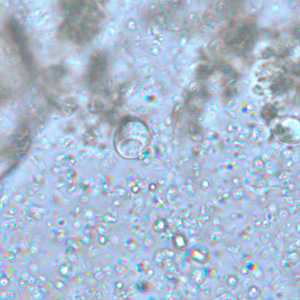

Figure A: Cyst of I. buetschlii in an unstained concentrated wet mount. In these cysts, the glycogen vacuole can be seen as a large, oval refractile body.

Figure B: Cyst of I. buetschlii in an unstained concentrated wet mount. In these cysts, the glycogen vacuole can be seen as a large, oval refractile body.